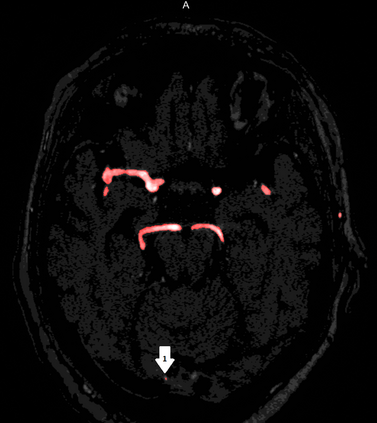

Deep learning approaches may help radiologists in the early diagnosis and timely treatment of cerebrovascular diseases. Accurate cerebral vessel segmentation of Time-of-Flight Magnetic Resonance Angiographs (TOF-MRAs) is an essential step in this process. This study investigates deep learning approaches for automatic, fast and accurate cerebrovascular segmentation for TOF-MRAs. The performance of several data augmentation and selection methods for training a 2D and 3D U-Net for vessel segmentation was investigated in five experiments: a) without augmentation, b) Gaussian blur, c) rotation and flipping, d) Gaussian blur, rotation and flipping and e) different input patch sizes. All experiments were performed by patch-training both a 2D and 3D U-Net and predicted on a test set of MRAs. Ground truth was manually defined using an interactive threshold and region growing method. The performance was evaluated using the Dice Similarity Coefficient (DSC), Modified Hausdorff Distance and Volumetric Similarity, between the predicted images and the interactively defined ground truth. The segmentation performance of all trained networks on the test set was found to be good, with DSC scores ranging from 0.72 to 0.83. Both the 2D and 3D U-Net had the best segmentation performance with Gaussian blur, rotation and flipping compared to other experiments without augmentation or only one of those augmentation techniques. Additionally, training on larger patches or slices gave optimal segmentation results. In conclusion, vessel segmentation can be optimally performed on TOF-MRAs using a trained 3D U-Net on larger patches, where data augmentation including Gaussian blur, rotation and flipping was performed on the training data.